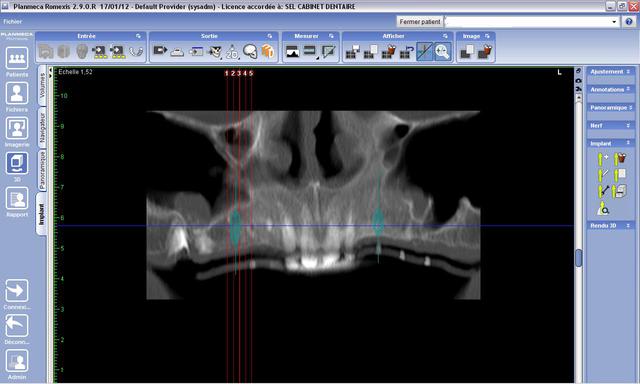

Voici le cas en photo, merci

Les 4 incisives sont conservables.

Solution proposée : stellite stabilisé sur locator avec implant 3.5 par 11.